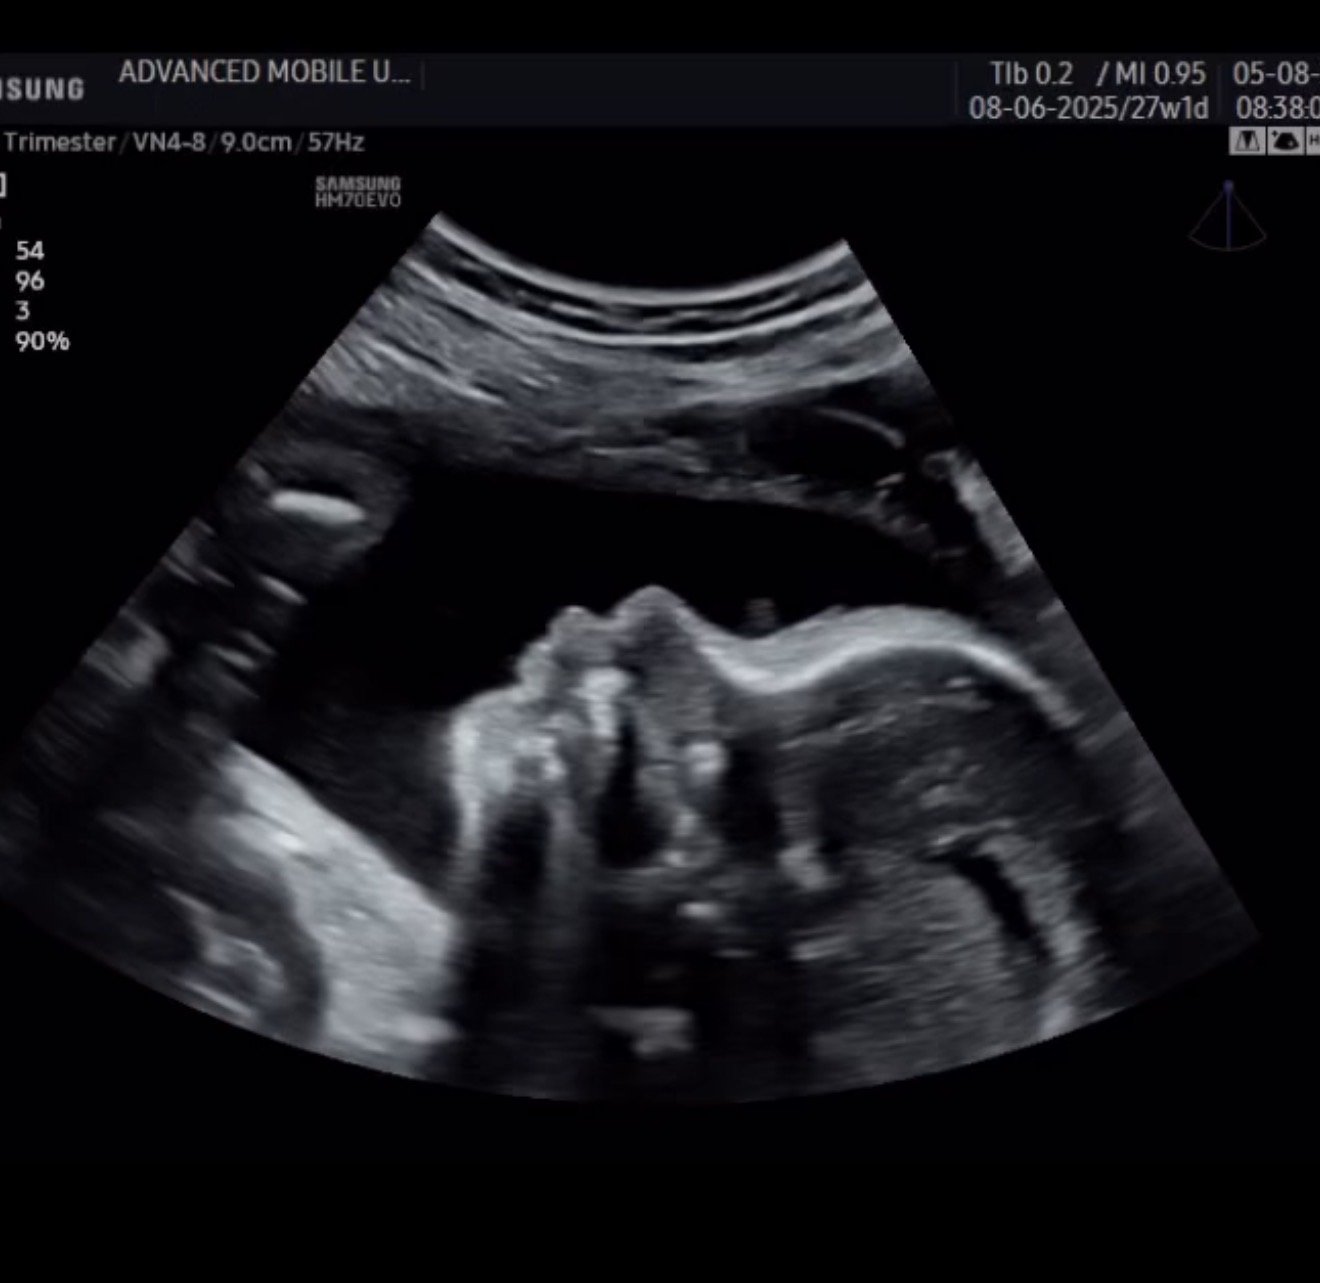

Pregnancy Ultrasounds (Elective & Diagnostic)

We offer both diagnostic and elective pregnancy ultrasounds performed by experienced, licensed sonographers using high-quality medical imaging equipment.

Diagnostic ultrasounds are medically indicated exams ordered by your provider to assess fetal development, confirm dates, evaluate concerns, or follow up on specific findings. These exams are interpreted by board-certified radiologists or physicians.

Elective ultrasounds are non-medical scans designed for bonding and reassurance, including early gender determination and 3D/4D imaging. These exams are not used for medical diagnosis and do not replace routine prenatal care.

She’s a wife and mom to four boys and a mobile sonographer with 5+ years of experience. She is registered in OB/GYN, Vascular, and Abdominal ultrasound. At AMU we work closely with Board Certified Radiologists and Cardiologists to ensure you have the best diagnostic ultrasound experience in home. We also offer elective ultrasound such as 3D/4D and early gender. We love perfecting 3D/4D images and giving you the best experience along your pregnancy journey! We can’t wait to serve your diagnostic needs and/or meet you and your wonderful baby!!